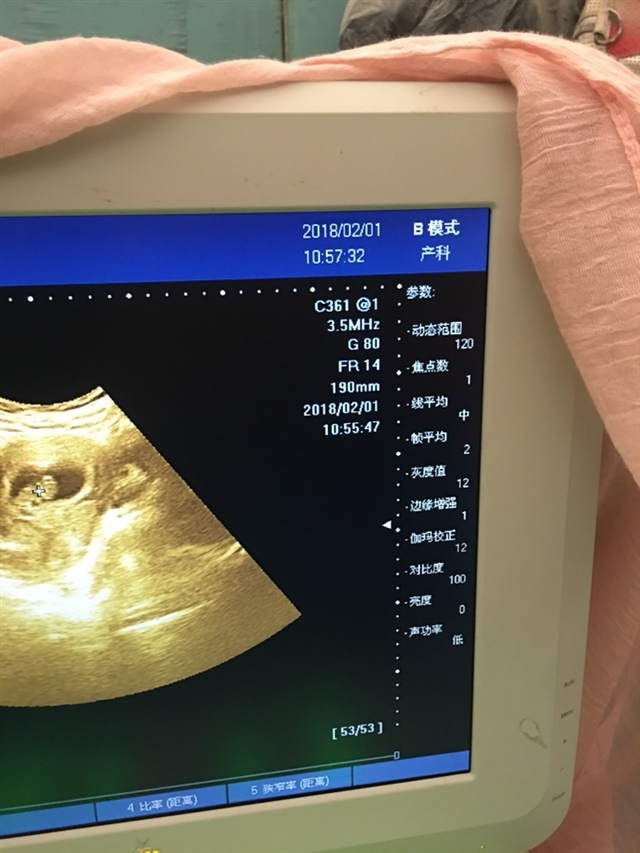

孕9周+5天

看到个可爱的宝宝。你这应该有11,12周了吧